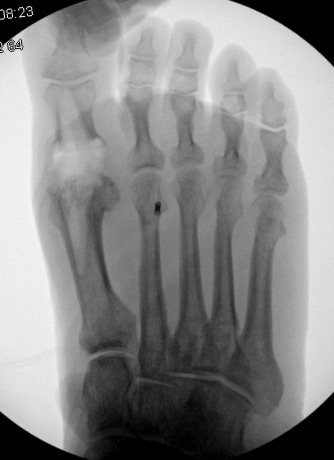

In foot and ankle surgery, common anatomical locations of bone harvest include the iliac crest, tibia, fibula and calcaneus. One tends to find the highest quality of bone for autogenous grafting in the sites closest to the axial skeleton. However, harvest is more difficult in these areas, as they require meticulous anatomic dissection to access the graft harvest site.9 There are several histological differences between these different anatomic sites as well which is important to harvest site selection. A surgeon must be able to estimate the amount of bone needed for harvest during the pre-operative planning process because positioning of the patient for the primary surgery may limit the surgeon's access to certain harvest sites. The surgeon should ensure that the appropriate instruments are available to perform proper harvest and implantation. Necessary instruments include drills, K-wires, trephines, bone saws, burrs, curettes, osteotomes, mallets and reamer-irrigator-aspirators.5

When it comes to harvest of autogenous bone from the posterior tuberosity of the calcaneus, surgeons most commonly utilize this harvest location for procedures in the midfoot and the forefoot.5 The calcaneus is a superior source of bone graft in terms of minimizing surgical time due to its close proximity to the primary surgical site. Calcaneal bone graft is a particularly useful compliment to arthrodesis procedures and fracture repair within the forefoot and the midfoot.

Biddinger and colleagues report that one can harvest up to three, eight mm trephine cores with minimal complication risk.16 DiDomenico and coworkers reported harvest of three to five cm3 of bone from the calcaneus using corticotomy and curettage while adding only two to three minutes of surgical time.17 The risk of sural nerve damage is low with the experienced surgeon but one should take care to avoid irritation in this area.15 Disadvantages of calcaneal bone graft include fracture risk, insufficient quality of bone and postoperative incisional irritation from footwear.18 If the calcaneus is unable to provide a sufficient volume of bone graft, a more proximal site of harvest may be necessary.5 Cross and DiDomenico characterize the calcaneus as a safe harvest site.19